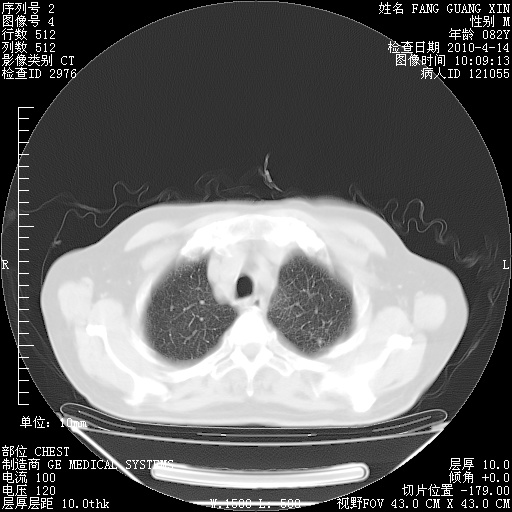

4月14日肺部CT